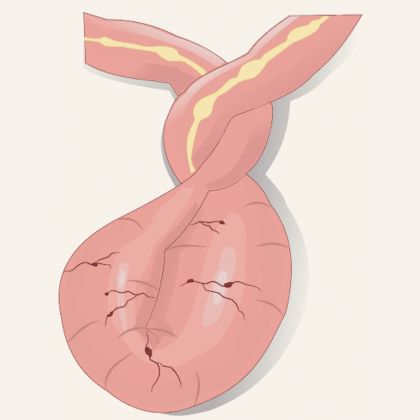

A. Skręt jelita (volvulus) – przyczyny i konsekwencje.

Skręt jelita, znany również jako volvulus, jest stanem, w którym jelito zatacza koło wokół własnej osi, prowadząc do blokady przepływu treści jelitowej.

- Przyczyną skrętu jelita może być nieprawidłowa anatomicznie długość lub ruchomość jelit, a także powstawanie zrostów jelit z innymi strukturami.

- Skręt jelita może prowadzić do zaburzeń krążenia jelitowego, niedokrwienia jelit, a w konsekwencji do martwicy jelita, co wymaga natychmiastowej interwencji chirurgicznej.